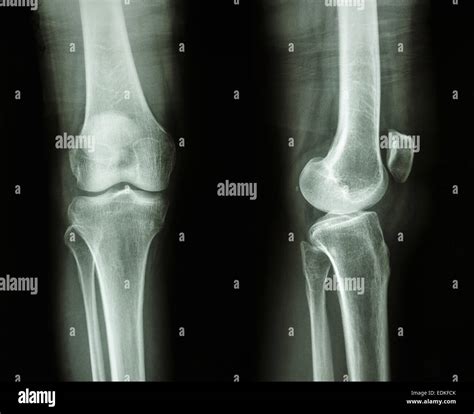

Lateral Knee Xray

A Lateral Knee Xray is a type of radiographic imaging that captures a side view of the knee joint. This view is essential for evaluating the alignment of the bones, the condition of the joint spaces, and the presence of any abnormalities such as fractures, dislocations, or arthritis. The lateral view complements other views, such as the anteroposterior (AP) and oblique views, to provide a comprehensive assessment of the knee.

Interpreting a Lateral Knee Xray requires a trained eye and knowledge of knee anatomy. Here are some key points to look for:

• Bone Alignment: Ensure that the bones are properly aligned. Any deviation can indicate a fracture or dislocation.

• Joint Spaces: Check the joint spaces for any narrowing, which can suggest arthritis or other degenerative conditions.

• Fractures: Look for any breaks or cracks in the bones, which can indicate a fracture.

• Soft Tissue Signs: While not always visible, soft tissue injuries can sometimes be inferred from the presence of joint effusion or other indirect signs.